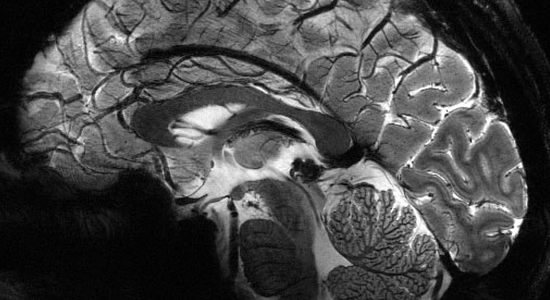

Comment se manifestent ces troubles ? De quelle manière le circuit

nerveux du traitement des odeurs est-il affecté ? Quelles solutions

existent pour tenter de récupérer son odorat ?